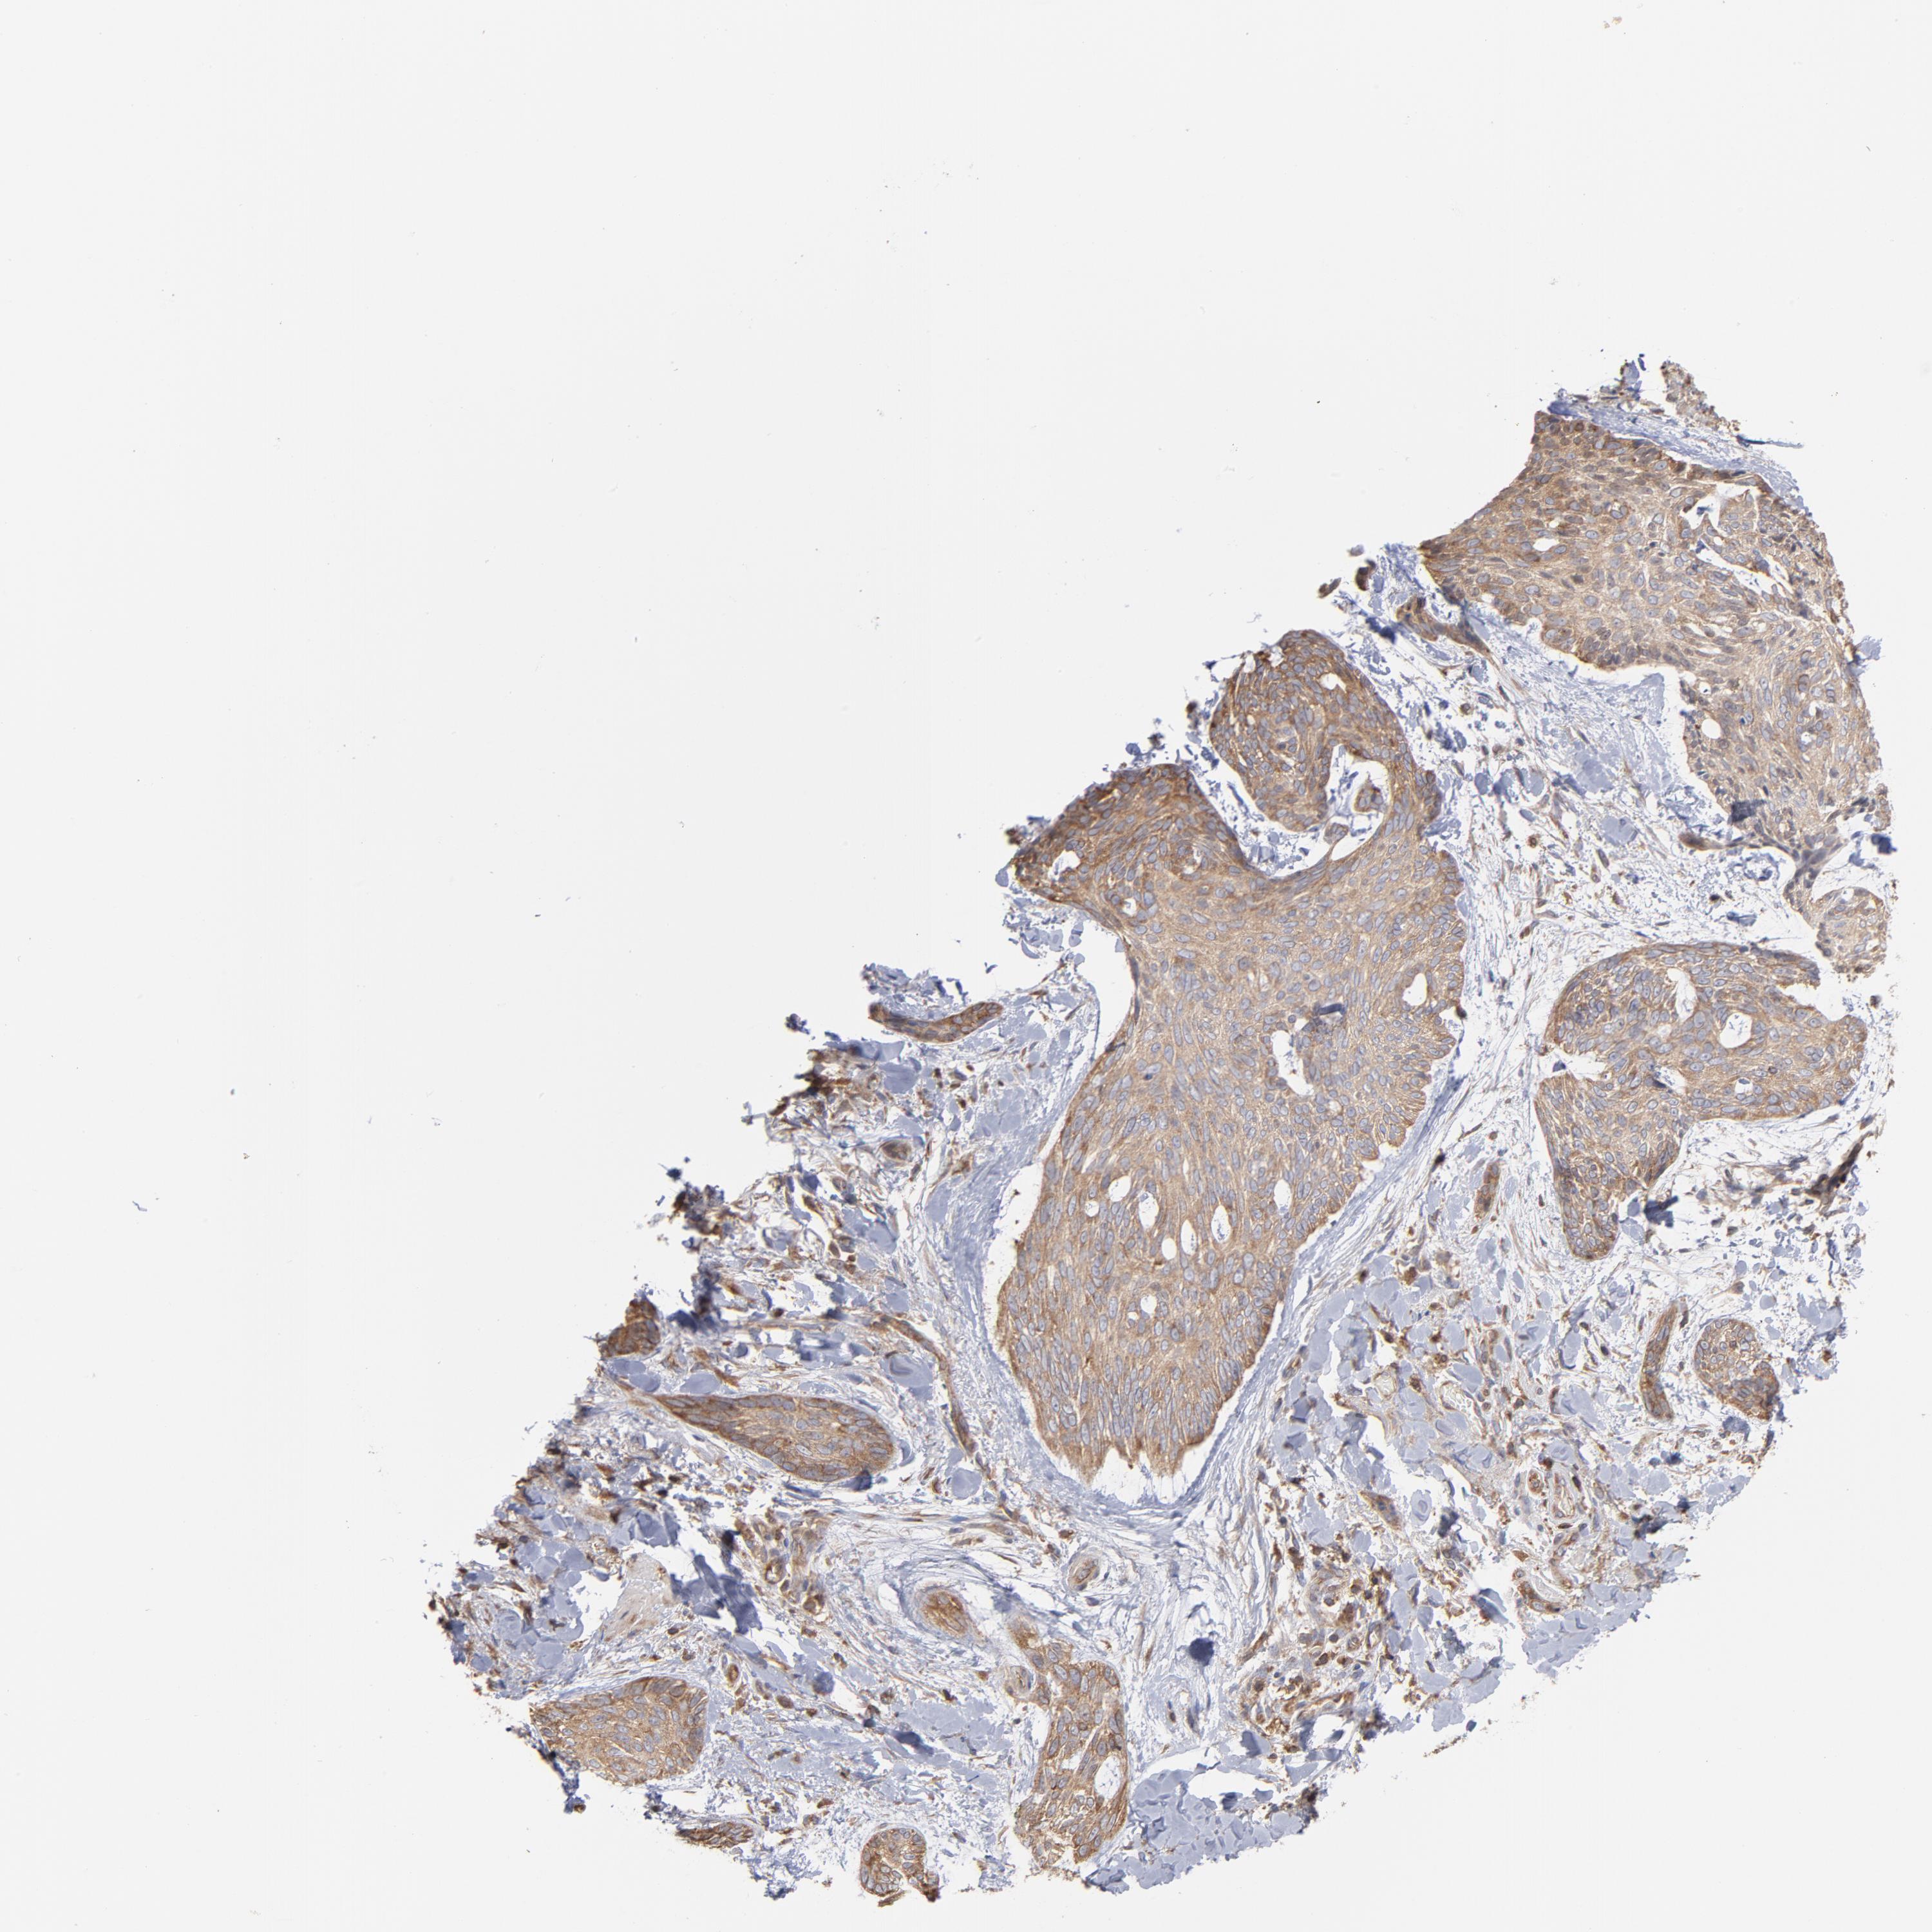

SKIN CANCER - Protein expressioni

A mouse-over function shows sample information and annotation data. Click on an image to view it in a full screen mode. Samples can be filtered based on level of antibody staining by selecting one or several of the following categories: high, medium, low and not detected. The assay and annotation is described here.

Antibody stainingi

Antibody staining in the annotated cell types in the current human tissue is reported as not detected, low, medium, or high, based on conventional immunohistochemistry profiling in selected tissues. This score is based on the combination of the staining intensity and fraction of stained cells.

Each image is clickable and will lead to virtual microscopy that enables deeper exploration of all samples and also displays staining intensity scores, fraction scores and subcellular localization as well as patient and tissue information for each sample.

Antibody HPA003600

Squamous cell carcinoma, NOS